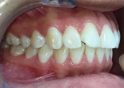

Classe II div 1, articulé croisé postérieur, surplomb accru, déviation de la ligne médiane maxillaire, rotations d'encombrement

État initial

État final

Résultats obtenus

- Relation de classe I obtenue

- Guidage fonctionnel des canines des deux côtés

- Articulé postérieur corrigé

- Surplomb et recouvrement normaux obtenus

- Surplomb amélioré

- Lignes médianes coïncidentes

- Bonne inclinaison axiale des incisives

- Courbe de Spee nivelée

- Forme de l'arcade améliorée